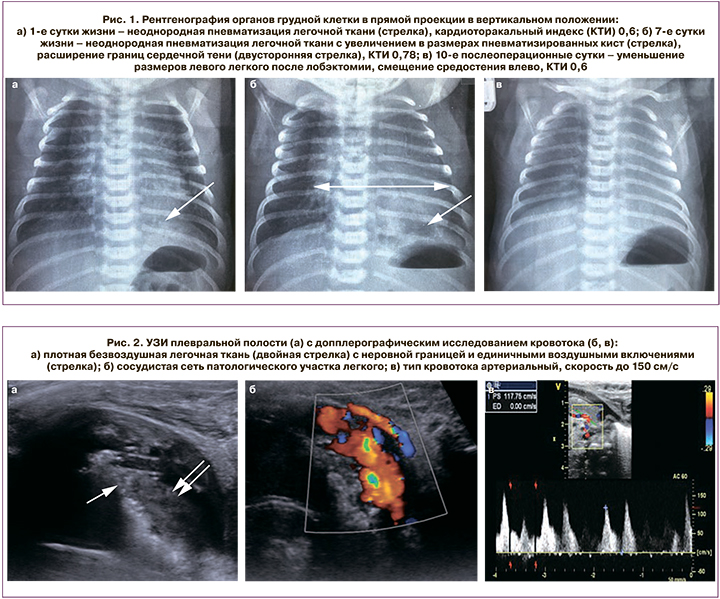

Роды II, своевременные физиологические, 8/9 баллов по Апгар; после рождения дыхание ребенка самостоятельное, признаки дыхательной недостаточности отсутствовали. По данным лабораторного обследования – лейкоцитоз 31,2 тыс./мкл со сдвигом лейкоцитарной формулы влево; по результатам обзорной рентгенографии органов грудной клетки в прямой проекции – зона неоднородной пневматизации легочной ткани в проекции нижней доли левого легкого без смещения средостения (рис. 1а); по данным УЗИ плевральных полостей – слева в ткани легкого определяется участок повышенной эхогенности размерами 30×25×28 мм с единичными локусами газа, визуализируется дополнительный крупный сосуд 2,8 мм с артериальным типом кровотока (рис. 2). По данным эхокардиографии (ЭхоКГ) в возрасте 2 ч жизни картина соответствовала возрасту – правый желудочек преобладал в размере относительно левого, функционировали артериальный проток диаметром 5,8 мм и межпредсердное сообщение размером 4,5 мм с перекрестным сбросом крови. С конца первых суток жизни у ребенка отмечали постепенное нарастание частоты дыхания до 60–70 в минуту, более выраженное при беспокойстве и физической нагрузке, к 6-м суткам жизни наблюдалось подключение к акту дыхания вспомогательной мускулатуры.

На 6-е сутки жизни выполнена мультиспиральная компьютерная томография (МСКТ) органов грудной клетки с контрастированием: в нижней доле левого легкого расположена зона измененной ткани, представленная мягкотканным компонентом в IX и X сегментах, с неровными нечеткими контурами, по периферии которого, с распространением на VII и VIII сегменты, имеются участки повышенной пневматизации с множественными мелкими воздушными кистами. При контрастировании определяются два аномальных питающих сосуда из нижнегрудного отдела аорты; дренирование крови осуществляется частично по аномальной вене в верхнюю полую вену и правое предсердие, частично по легочным венам в левое предсердие. Остальные отделы правого и левого легких структурно не изменены. Данные изменения соответствуют комбинации интралобарного секвестра и врожденной кистозно-аденоматозной мальформации нижней доли левого легкого (рис. 3).

При ЭхоКГ на 7-е сутки жизни впервые выявлены расширение правых и левых отделов сердца, появление признаков легочной гипертензии, недостаточности митрального и трикуспидального клапанов. При сравнении данных обзорной рентгенографии грудной клетки на 1-е и 7-е сутки жизни выявлено нарастание КТИ с 0,6 до 0,78 (рис. 1б). С учетом сохраняющегося лейкоцитоза заподозрена манифестация инфекционного процесса, начат курс антибактериальной терапии, однако существенной динамики в состоянии ребенка не отмечено. По данным ЭхоКГ на 8-е сутки жизни – отрицательная динамика – нарастание право- и левожелудочковой сердечной недостаточности, легочной гипертензии, митральной и трикуспидальной недостаточности. При клиническом наблюдении сохраняется одышка, снижается темп диуреза. Совместно с детским кардиологом и реаниматологом проведен анализ имеющихся клинических и инструментальных данных – учитывая отсутствие структурных изменений сердца по данным ЭхоКГ и МСКТ, нарастание признаков сердечной недостаточности, вероятно, связано с гемодинамическими особенностями порока развития легкого – массивным шунтированием крови слева-направо и слева-налево через аномальные сосуды секвестра легкого.

По результатам клинического наблюдения (купирование одышки, нормальные размеры печени), динамических Эхо-КГ (нормализация давления в правых отделах сердца и сокращения до нормальных размеров сердечных камер, отсутствие недостаточности на атриовентрикулярных клапанах), рентгенологических данных (нормализация КТИ) и в соответствии с рекомендациями кардиолога из терапии постепенно исключены инотропный препарат, диуретические и вазоактивные средства. При осмотре перед выпиской домой дыхание равномерно проводится во все отделы грудной клетки, хрипов нет, данных за дыхательную и сердечную недостаточность нет. По результатам УЗИ и рентгенографии легкие воздушны, признаков пневмоторакса и гидроторакса нет (рис. 1в). Ребенок выписан домой на 11-е послеоперационные сутки в удовлетворительном состоянии, спокойно перенес длительный авиаперелет из столицы в отдаленный регион страны. Катамнез в настоящее время составляет 4 месяца, отклонений в состоянии здоровья при наблюдении профильных специалистов и по данным инструментальных исследований нет.